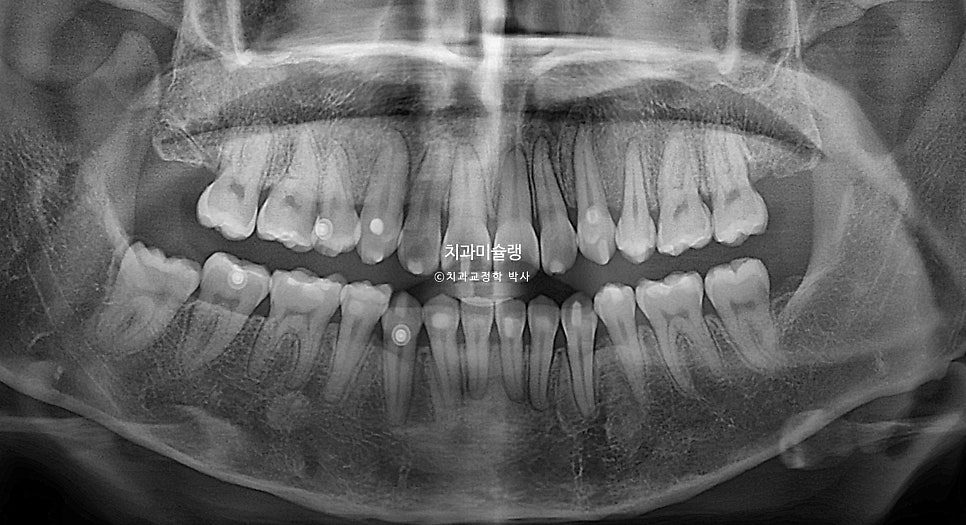

드디어 임신 출산까지 끝났기에 오랜만에 엑스레이를 찍어보니

세 번째 재제작

치아 뿌리가 간격이 일부에서 약간 아쉽습니다.

사실 엑스레이를 찍지 않으면 알수 없는 부분이고, 장기적으로 교정 결과나 구강 건강에 문제되는 부분도 아니지만

아무래도 치근 평행도가 아쉬워 이부분 개선을 위해 재제작 하자고 환자분을 꼬셨습니다.(?)

교정치료 기간 토탈 2년 5개월동안 재제작을 총 3번 했는데, 만약 재제작 할 당시 엑스레이를 찍어 중간 중간 뿌리 평행도를 확인했다면 재제작 횟수를 1회정도는 줄일 수 있었겠죠.

2년 5개월간 치근흡수는 없었으며

마지막 재제작으로 인해 치근 평행도까지 완벽해졌습니다.